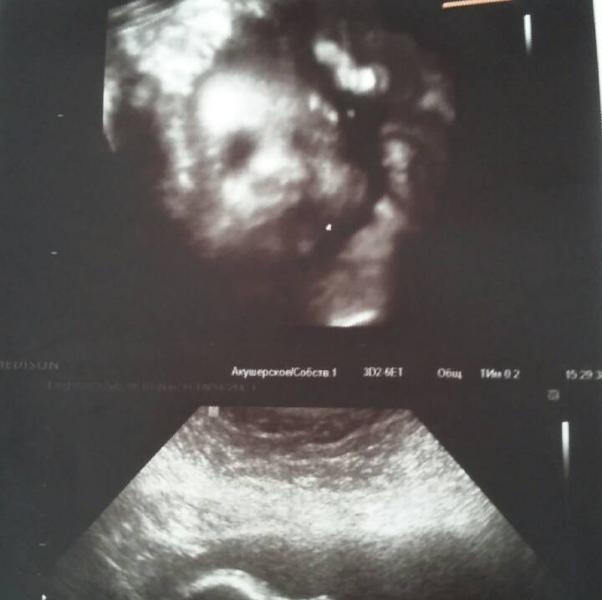

Вот и моя малышка. Сходили на 3д. У нас все хорошо. Патологий нет. Только вес меня смущает-1525гр. Какие ваши были малыши на этом сроке? Кстати, наконец-то узнали пол: девочка 100% сказали. Мы с палочкой рады нашей принцессе 😙